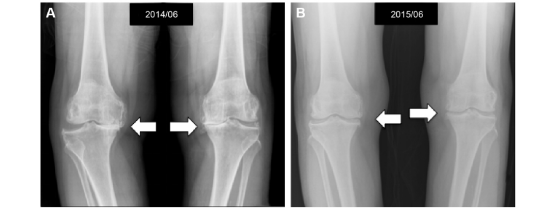

图为膝骨关节炎患者注射PRP后膝关节影像学改变。